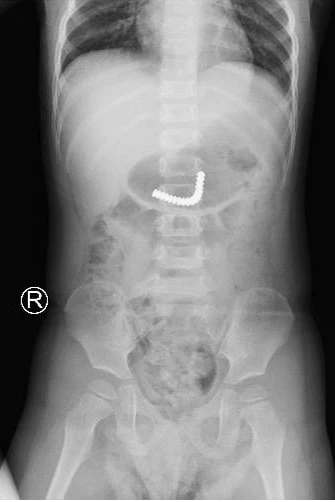

Hình ảnh 18 viên nam châm dính chùm trong ruột bé trai. Ảnh: BVCC

Bé được chụp phim kiểm tra thấy dị vật trong dạ dày nên được đưa đi nội soi tiêu hoá khẩn thì thấy dị vật đã xuống ruột non. Do đó, các bác sĩ trong tua trực quyết định khẩn trương mổ nội soi thám sát.

BS CK1 Đỗ Huy Trọng Hiếu, Khoa Ngoại Tổng hợp kể lại, các bác sĩ đã nhẹ nhàng đưa đoạn ruột phình chứa dị vật ra vết mổ chỗ rốn, mở hỗng tràng lấy dị vật là 18 viên nam châm dính chùm. Sau mổ, bé đang hồi phục tốt và dự kiến xuất viện vài ngày tới.